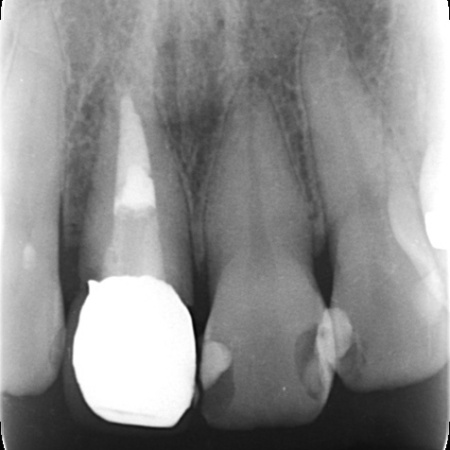

拝見したところ、右上前歯(中切歯)は歯根が折れて温存が難しく、抜歯が必要な状態でした。

まずは歯根が折れた右上前歯を抜き、その直後にインプラントの埋入手術を行います。これは抜歯即時埋入といい、治療期間の短縮が期待できる方法です。

手術の際は、インプラント周囲の骨を強化するための骨移植と、歯肉の厚みを確保するための歯肉移植を併せて行いました。この処置により、インプラントの長期的な維持と、自然な歯肉のラインの実現を目指します。